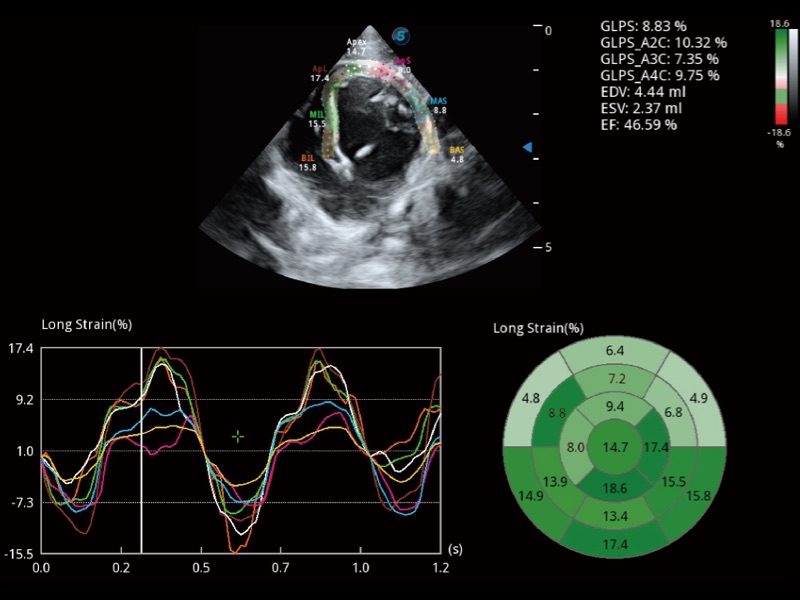

能够基于左心室壁追踪和辛普森法,自动计算射血分数,支持多个可移动点描迹,与手动测量相比,极大节省了动物医生的时间和精力。

具备多种协议可选,同时支持17阶段划分法和专业的SE报告。

实时用颜色表示心肌组织运动,观察和定量组织的运动情况,对快速检测与评估心肌的灌注和活性、电传导及心肌收缩和舒张功能等均能提供重要的诊断信息。